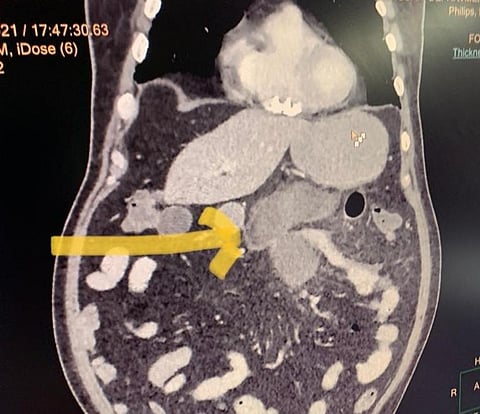

डॉ. धीर ने कहा, सीटी स्कैन (CT scan) से पता चला कि कुमार की छोटी आंत (जेजुनम) में छेद हो गया था। (सांकेतिक चित्र, Pixabay)

डॉ. धीर ने कहा, सीटी स्कैन (CT scan) से पता चला कि कुमार की छोटी आंत (जेजुनम) में छेद हो गया था। उनकी कोविड की बीमारी भी अब गंभीर हो गई थी और वेंटिलेटर सपोर्ट की आवश्यकता हो गई थी। मरीज को भर्ती कराया गया और सर्जरी के लिए तत्काल ले जाया गया।

उनकी नैदानिक जांच में भी आंतों में छिद्र के कोई लक्षण नहीं दिखे। फिर भी, संदेह के आधार पर सर गंगा राम अस्पताल में मेडिकल गैस्ट्रोएंटरोलॉजी के वरिष्ठ सलाहकार डॉ. पीयूष रंजन ने रोगी के लिए एक तत्काल सीटी स्कैन कराने की सलाह दी।